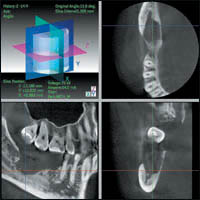

Анализ клинического материала Рентгенодиагностического центра Системы клиник МЕDИ (Санкт-Петербург, Москва) показывает, что 3DХ Accuitomo/FPD:

— позволяет провести дифференциальную диагностику осложнений кариеса зубов и определить оптимальную методику и тактику эндодонтического лечения (рис. 4);

— дает возможность прогнозировать и оценивать отдаленные результаты имплантации и хирургического лечения у пациентов стоматологических клиник (рис. 5);

— позволяет проводить оценку результатов ортопедического и ортодонтического лечения стоматологических пациентов

(рис. 6);

— дает возможность выявлять патологические изменения со стороны верхнечелюстных пазух, полости носа, нижнечелюстного канала (рис. 7);

— расширяет возможности в диагностике височно-нижнечелюстных суставов, наружного слухового прохода, среднего и внутреннего уха (рис. 8).